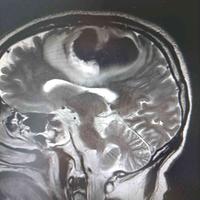

发现颅内占位5天,脑膜瘤?

发现颅内占位5天,脑膜瘤?...

由 medjpg 发表于 2026-03-24 22:32